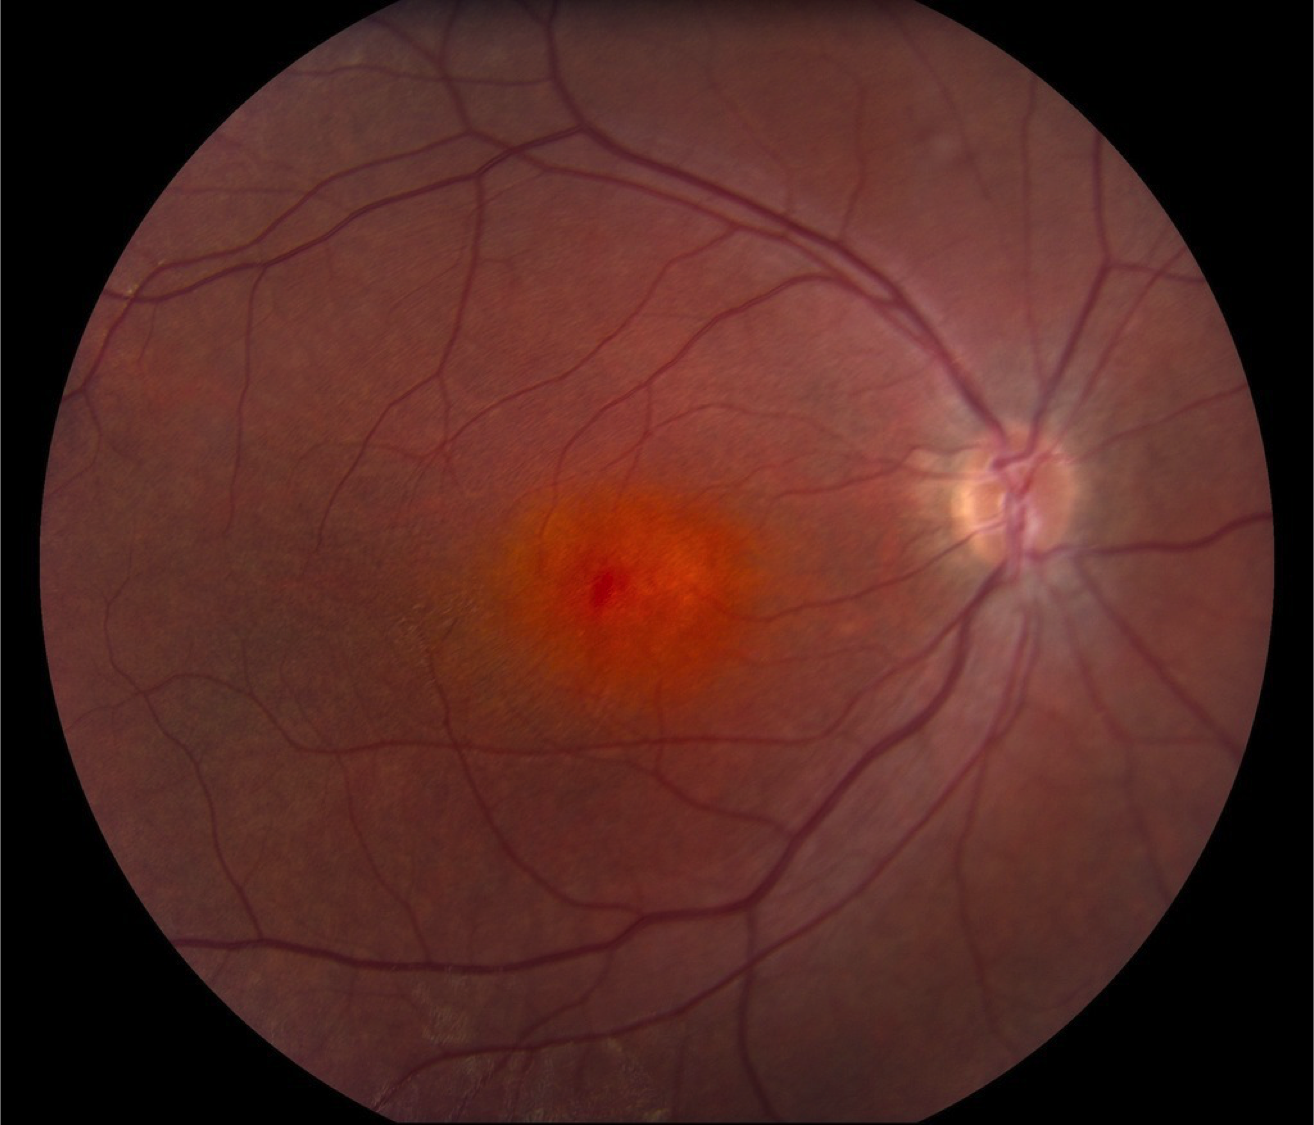

Case 15 is 5 years old and has 20/40 visual acuity. His normally sighted parents noticed that he bumped into things inexplicably shortly after he began to walk. They sought medical attention and he was given hyperopic spectacles of about 4 diopters which seemed to help with his central vision. However, his parents still suspected that his peripheral field was constricted because he would back up to find things. Electroretinography was then performed which revealed reduced scotopic responses and completely extinguished photopic responses. Goldmann perimetry revealed a V4e isopter about 50 degrees in diameter.

Color fundus photograph of the right eye.